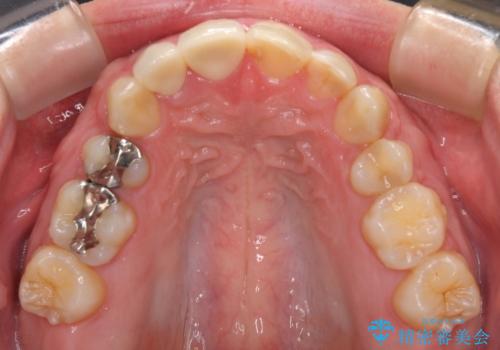

当初は1番目立つ1本だけをご希望でしたが、相談の結果、隣の歯(神経が抜いてあり金属が入っている歯)と2本同時に製作することになりました。

上の前歯など審美性の要求が高くなる部位については、数本同時に製作することで色をそろえることが可能です。

患者様は前歯の見た目の改善を主訴にご来院されました。上の前歯6本とも古いつめものがつぎはぎになっていましたが、まずは1番目立つところを治すことをご希望でした。相談の結果、今回は2本できれいになるように工夫しました。